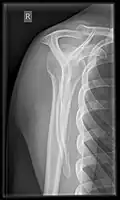

- Humerus - AP and Lateral

- Elbow - AP and Lateral. Radial head projections available on request